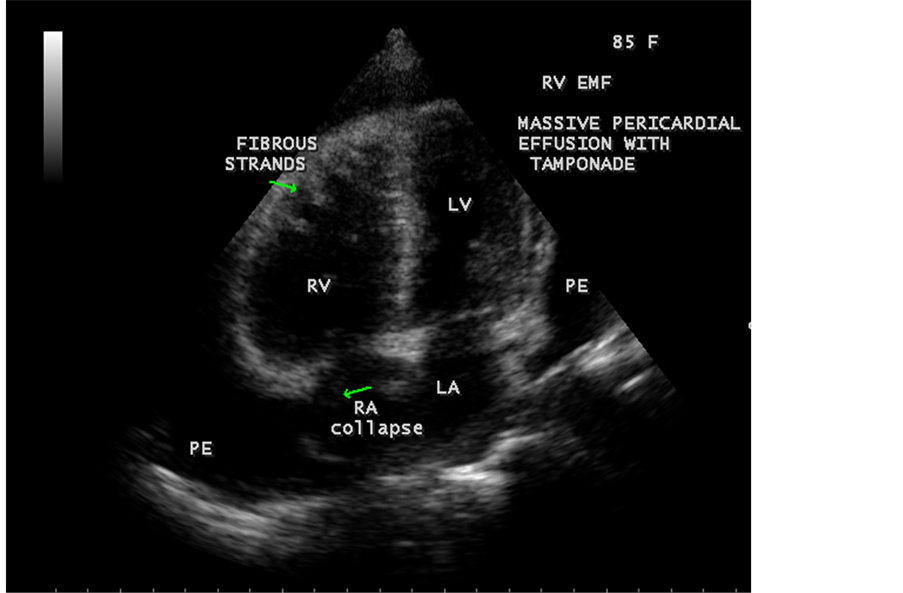

A 85-year-old obese female was admitted in the cardiac intensive care unit with sudden onset of breathlessness. X-ray chest revealed massive pericardial effusion with calcification in the right ventricular region as shown in Figure 16. ECG revealed low voltage complexes. Blood chemistry revealed normal. Transthoracic echocardiography revealed large pericardial effusion with Right ventricular apical fibrosis, suggesting right ventricular endomyocardial fibrosis as shown in Figure 17 with tamponade physiology as in Figure 18 and treated with pericardiocentesis and pericardial fluid revealed an exudate on biochemical analysis.

Figure 17. Apical four chamber view suggesting RV apical fibrosis with massive pericardial effusion.

Figure 18. Pulsed-doppler imaging showing tamponade physiology.

A large pericardial effusion is often present and noted as another peculiar feature of this disease [27] . Pericardial effusion and ascites dominate the clinical picture of right ventricular EMF [28] [29] [30] . Etiology of pericardial effusion is possibly inflammatory and EMF is to be considered as “pancarditis” since all the layers are involved. Adhesions between the parietal and visceral layers of the pericardial sac may develop and visible as strong fibrotic strands as shown in Figure 29. A right ventricular EMF presented with massive pericardial effusion was detected in a 85-year-old female as shown in Figure 16, Figure 17 and Figure 18 [31] . Cardiomegaly can be exaggerated by pericardial effusion, and pleural effusion is also a common finding as shown in Figure 9 ( [16] , Figure 2).